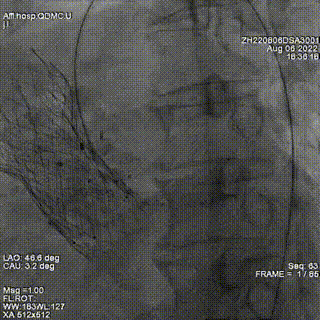

超声提示2枚封堵器位置良好,瓣周反流明显减少,但仍有少-中量瓣周反流。遂在已植入封堵器旁再次探查,并通过瓣周漏。因交换鞘管困难,遂采用LOOP法建立轨道,引导输送鞘管通过瓣周漏。

释放第三枚封堵器,选用6mmADOII,释放后造影显示无明显瓣周反流。